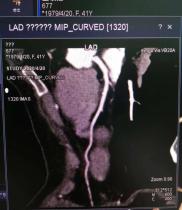

鄂托克前旗人民医院放射科最新引进西门子64排128层螺旋CT,于4月22日开展了首例冠脉CTA检查。64排128层螺旋CT与16排、32排CT相比,可以让临床医生看到更多更为精确的细节,其层厚更薄,扫描时间更短,辐射剂量更少,图像更清晰,功能更强大。可提高冠心病,脑血管疾病,各种肿瘤等诊断准确率,同时有利于各种疾病的预后评估与早期筛查。

其独具的无创、高效、精确、立体的医学影像技术,在检查状动脉有无狭窄、搭桥、支架的形态学以及心功能分析上有较强的优越性。实现了冠状动脉的无创检查,有着显影快、图像清晰的独特优势,并解决了心率及容积效应等主要影响图像质量的因素,为冠心病的筛选普查及诊断提供了一种安全、迅速、费用低廉的检查方法。此外,64排螺旋CT不但可以进行形态学的诊断,还可以用于功能成像诊断,如脑灌注成像的应用等,可以早期显示脑缺血灶。因扫描速度快,64排螺旋CT在急诊医学及早期肺栓塞的诊断上有独特优势,还可用于筛选冠心病、肺癌、肝硬化等,并进行良性与恶性肿瘤的分析。